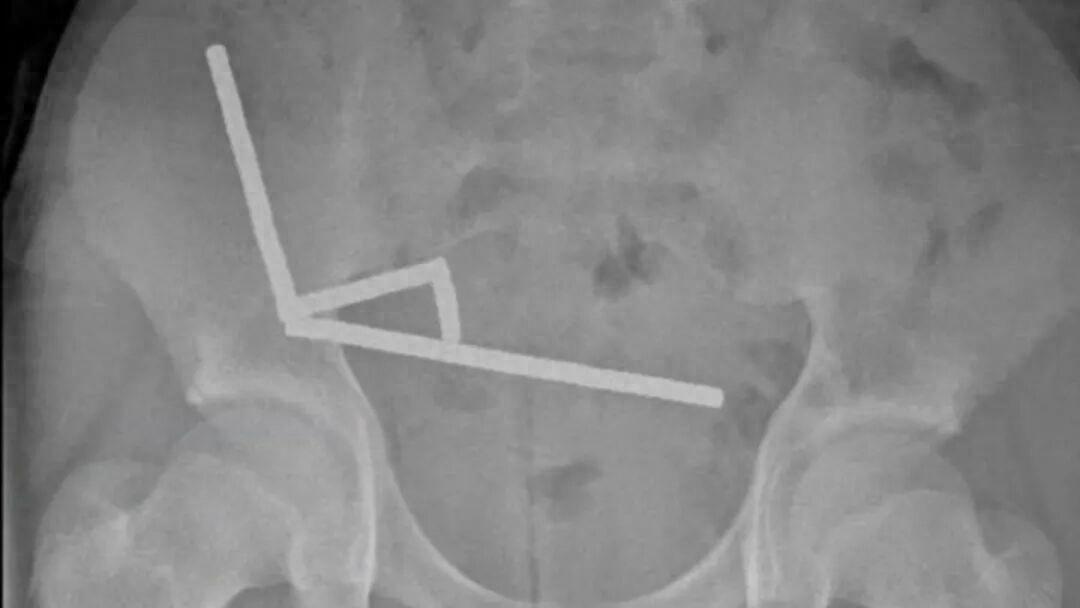

一位13歲的新西蘭男孩因爲腹部疼痛到醫院就診。在X光片檢查中,醫生髮現他的下腹部出現了由幾根筆直“線條”構成的詭異圖案。

男孩的腹部X光片 | Lekamalage et al., NZMJ, 2025

這些“線條”的真面目是將近200塊強磁鐵,男孩承認,自己在大約一週前把它們吞進了肚子。互相吸引的磁鐵狠狠地擠壓着男孩的腸道,已經造成多處組織壞死。在去除磁鐵時,醫生不得不將壞死的腸道一併切除[1]